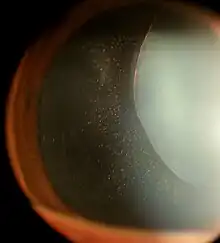

Zonules of Zinn visible in a case of an exceptionally dilated pupil with lens subluxation in Marfan syndrome

The zonules of Zinn are difficult to visualize using a slit lamp, but may be seen with exceptional dilation of the pupil, or if a coloboma of the iris or a subluxation of the lens is present.[8] The number of zonules present in a person appears to decrease with age.[5] The zonules insert around the outer margin of the lens (equator), both anteriorly and posteriorly.[9]